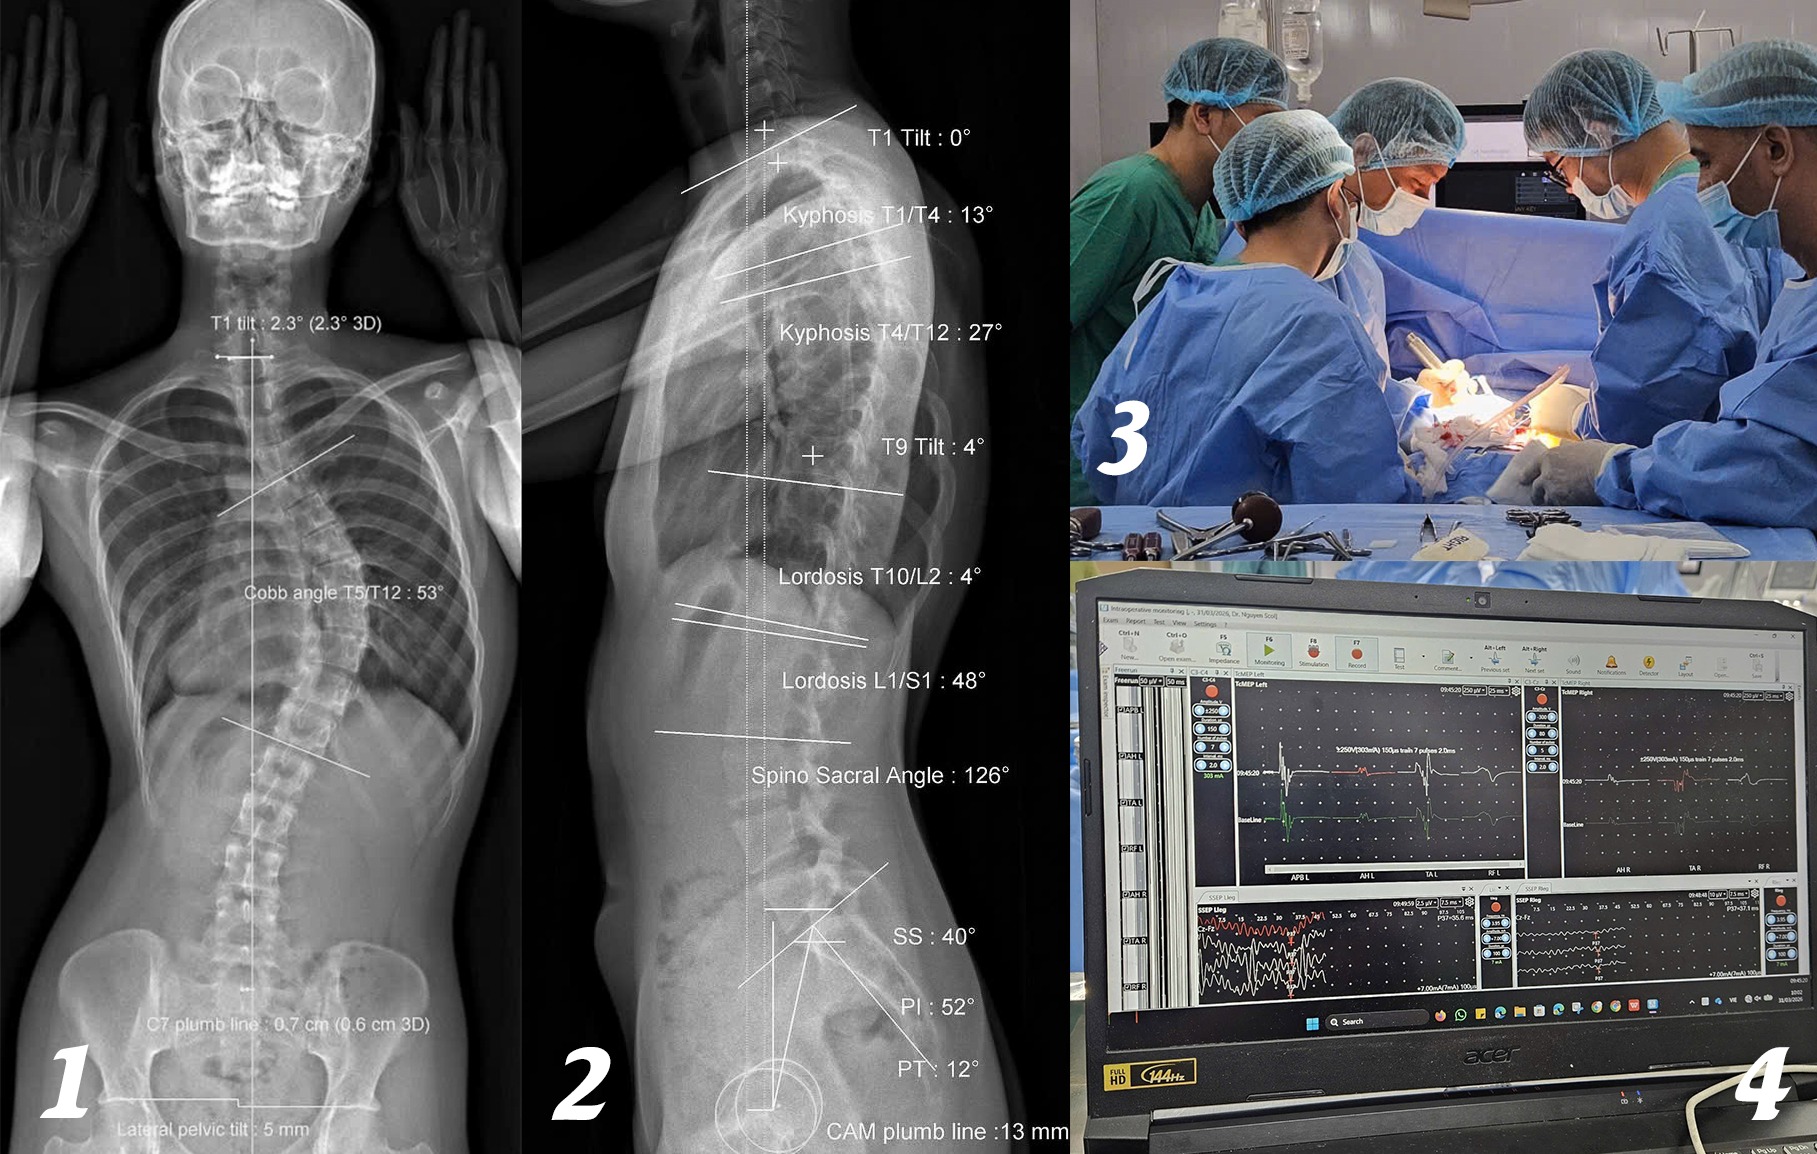

Hình ảnh EOS cho thấy người bệnh vẹo cột sống ngực 53 độ. Sau đó, các bác sĩ tiến hành phẫu thuật cùng với hệ thống IOM cảnh báo thần kinh trong phẫu thuật cột sống.

Tại đây, D. được chụp EOS (chụp quang tuyến thấy toàn bộ trục xương của cơ thể) và thăm khám. Kết quả cho thấy cột sống cô bị vẹo 53 độ, mức độ nghiêm trọng, có nguy cơ ảnh hưởng đến thẩm mỹ, tâm lý và chức năng vận động nếu không được điều trị kịp thời.

Trong quá trình phẫu thuật, các bác sĩ đã tính toán kỹ lưỡng, nắn chỉnh các đốt sống bằng hệ thống vít ốc chuyên dụng để giúp cột sống của cô trở lại mức sinh lý nhất có thể. Sau 4 giờ, ca phẫu thuật thành công.

Điểm nổi bật của ca phẫu thuật này là việc ứng dụng hệ thống IOM (theo dõi điện sinh lý thần kinh trong mổ). Hệ thống này giúp giám sát liên tục tín hiệu thần kinh, kịp thời cảnh báo nguy cơ tổn thương tủy sống, biến chứng nặng có thể dẫn đến liệt. Nhờ đó, ê-kíp phẫu thuật có thể điều chỉnh thao tác ngay trong quá trình mổ, đảm bảo an toàn tối đa cho chức năng vận động của bệnh nhân.